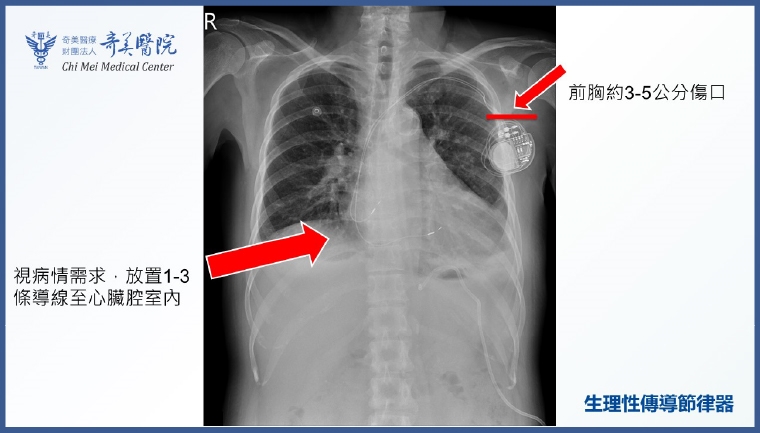

黃沛頡醫師指出,體內心臟節律器置放至今已有接近70年之歷史,安全性與成效皆相當成熟。近十多年來,因科學及技術的進步,醫學界更研發出了「生理性傳導」技術。不同於傳統節律器,有時會因心室收縮不同步,進而引發「節律器引起之心衰竭」;生理性傳導技術透過「希氏束」、「左束支」及「巴赫曼氏束」進行精準起搏,能夠提供病人更加天然、自然的節律。多項臨床研究證實,這種方式能減緩心臟功能下降、減少心房顫動復發,對於特定病人甚至能改善心臟衰竭症狀。

黃沛頡醫師進一步說明,根據統計,台灣約二十年前每年有2,000至4,000名病人接受心臟節律器置放。近年來,每年需要心臟節律器的病人數量逐漸增加到約7,500人。針對日益增加的節律器需求,奇美醫院近年在「心室型生理性傳導」技術已累積成熟經驗。2025年更進一步引進心房型「巴赫曼氏束」生理性傳導技術,提供全方位的生理性節律。雖然生理性傳導技術因需精準定位,手術時間會比傳統手術多出0.5至1.5小時,且須視病人解剖構造決定能否施作,但在適合的條件下,可大幅提升治療品質。